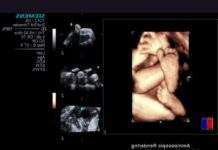

Дитини в утробі розглянуть у стереоокулярах

Nvidia і Siemens Healthcare продемонстрували нову технологію ультразвукового 3D сканування, що дозволяє майбутнім батькам і акушерам побачити плід з високим рівнем деталізації за допомогою 3D-очок.